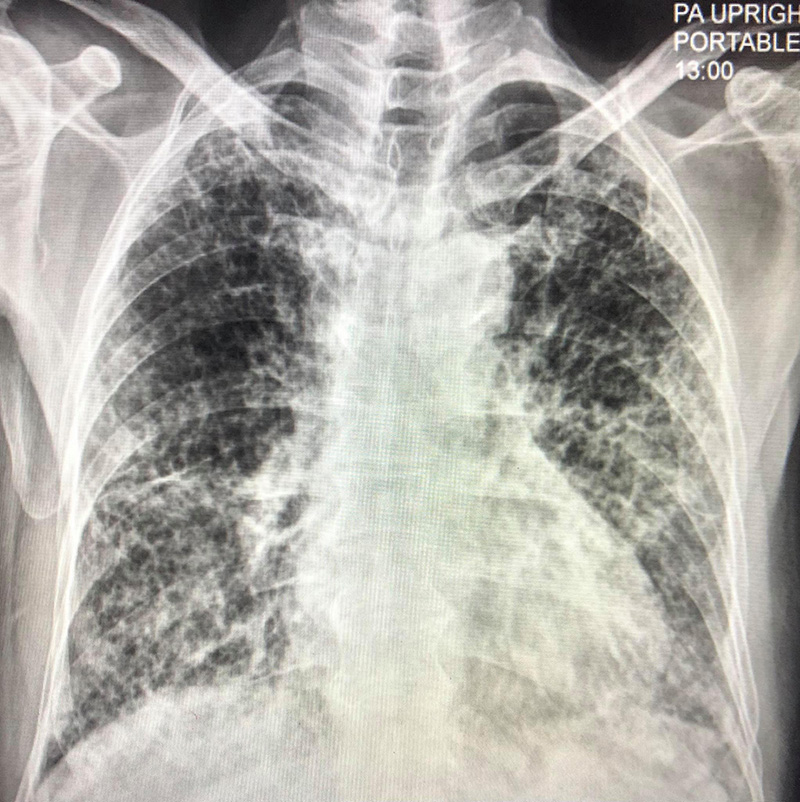

สำหรับเจ้าของปอดรายนี้ เป็นชายไทยวัย 80 ปี ไม่ดื่มเหล้า ไม่สูบบุหรี่ ติดเชื้อจากลูกหลานที่มาเยี่ยม เมื่อเอกซเรย์ปอดพบฝ้าขาว 2 ข้าง พอสแกนปอดพบเนื้อเยื่อปอดอักเสบรุนแรง มีทั้งฝ้าขาว รอยโรคเหมือนร่างแห และลักษณะผิดปกติคล้ายรังผึ้งกระจายทั่วไป

ส่วนการรักษาต้องใช้ออกซิเจนมากถึง 10 ลิตรต่อนาทีตลอดเวลา นอนรักษาตัวที่โรงพยาบาลตั้งแต่ 16 เมษายน ถึง 22 พฤษภาคม 2564